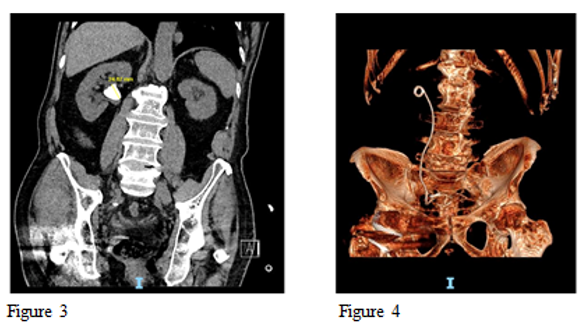

Figure 1 Pre op Large 21 mm Partial staghorn stone and Figure 2 Post op 3 D reconstructed CT scan showing complete clearance of stone after single procedure using High Power Holmium Laser.

Figure 3 Pre op Large renal pelvic stone 24mm and Figure 4 Post op 3d reconstructed CT scan showing complete clearance of the stone after single procedure using High Power Holmium Laser.